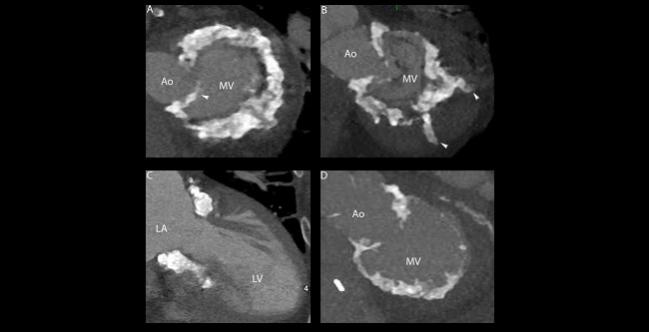

Photo Credit: Ailawadi G. TENDYNE: Attributes, Challenges, and Clinical Data (SUMMIT). Presented at: TVT 2019. June 14, 2019. Chicago, IL.